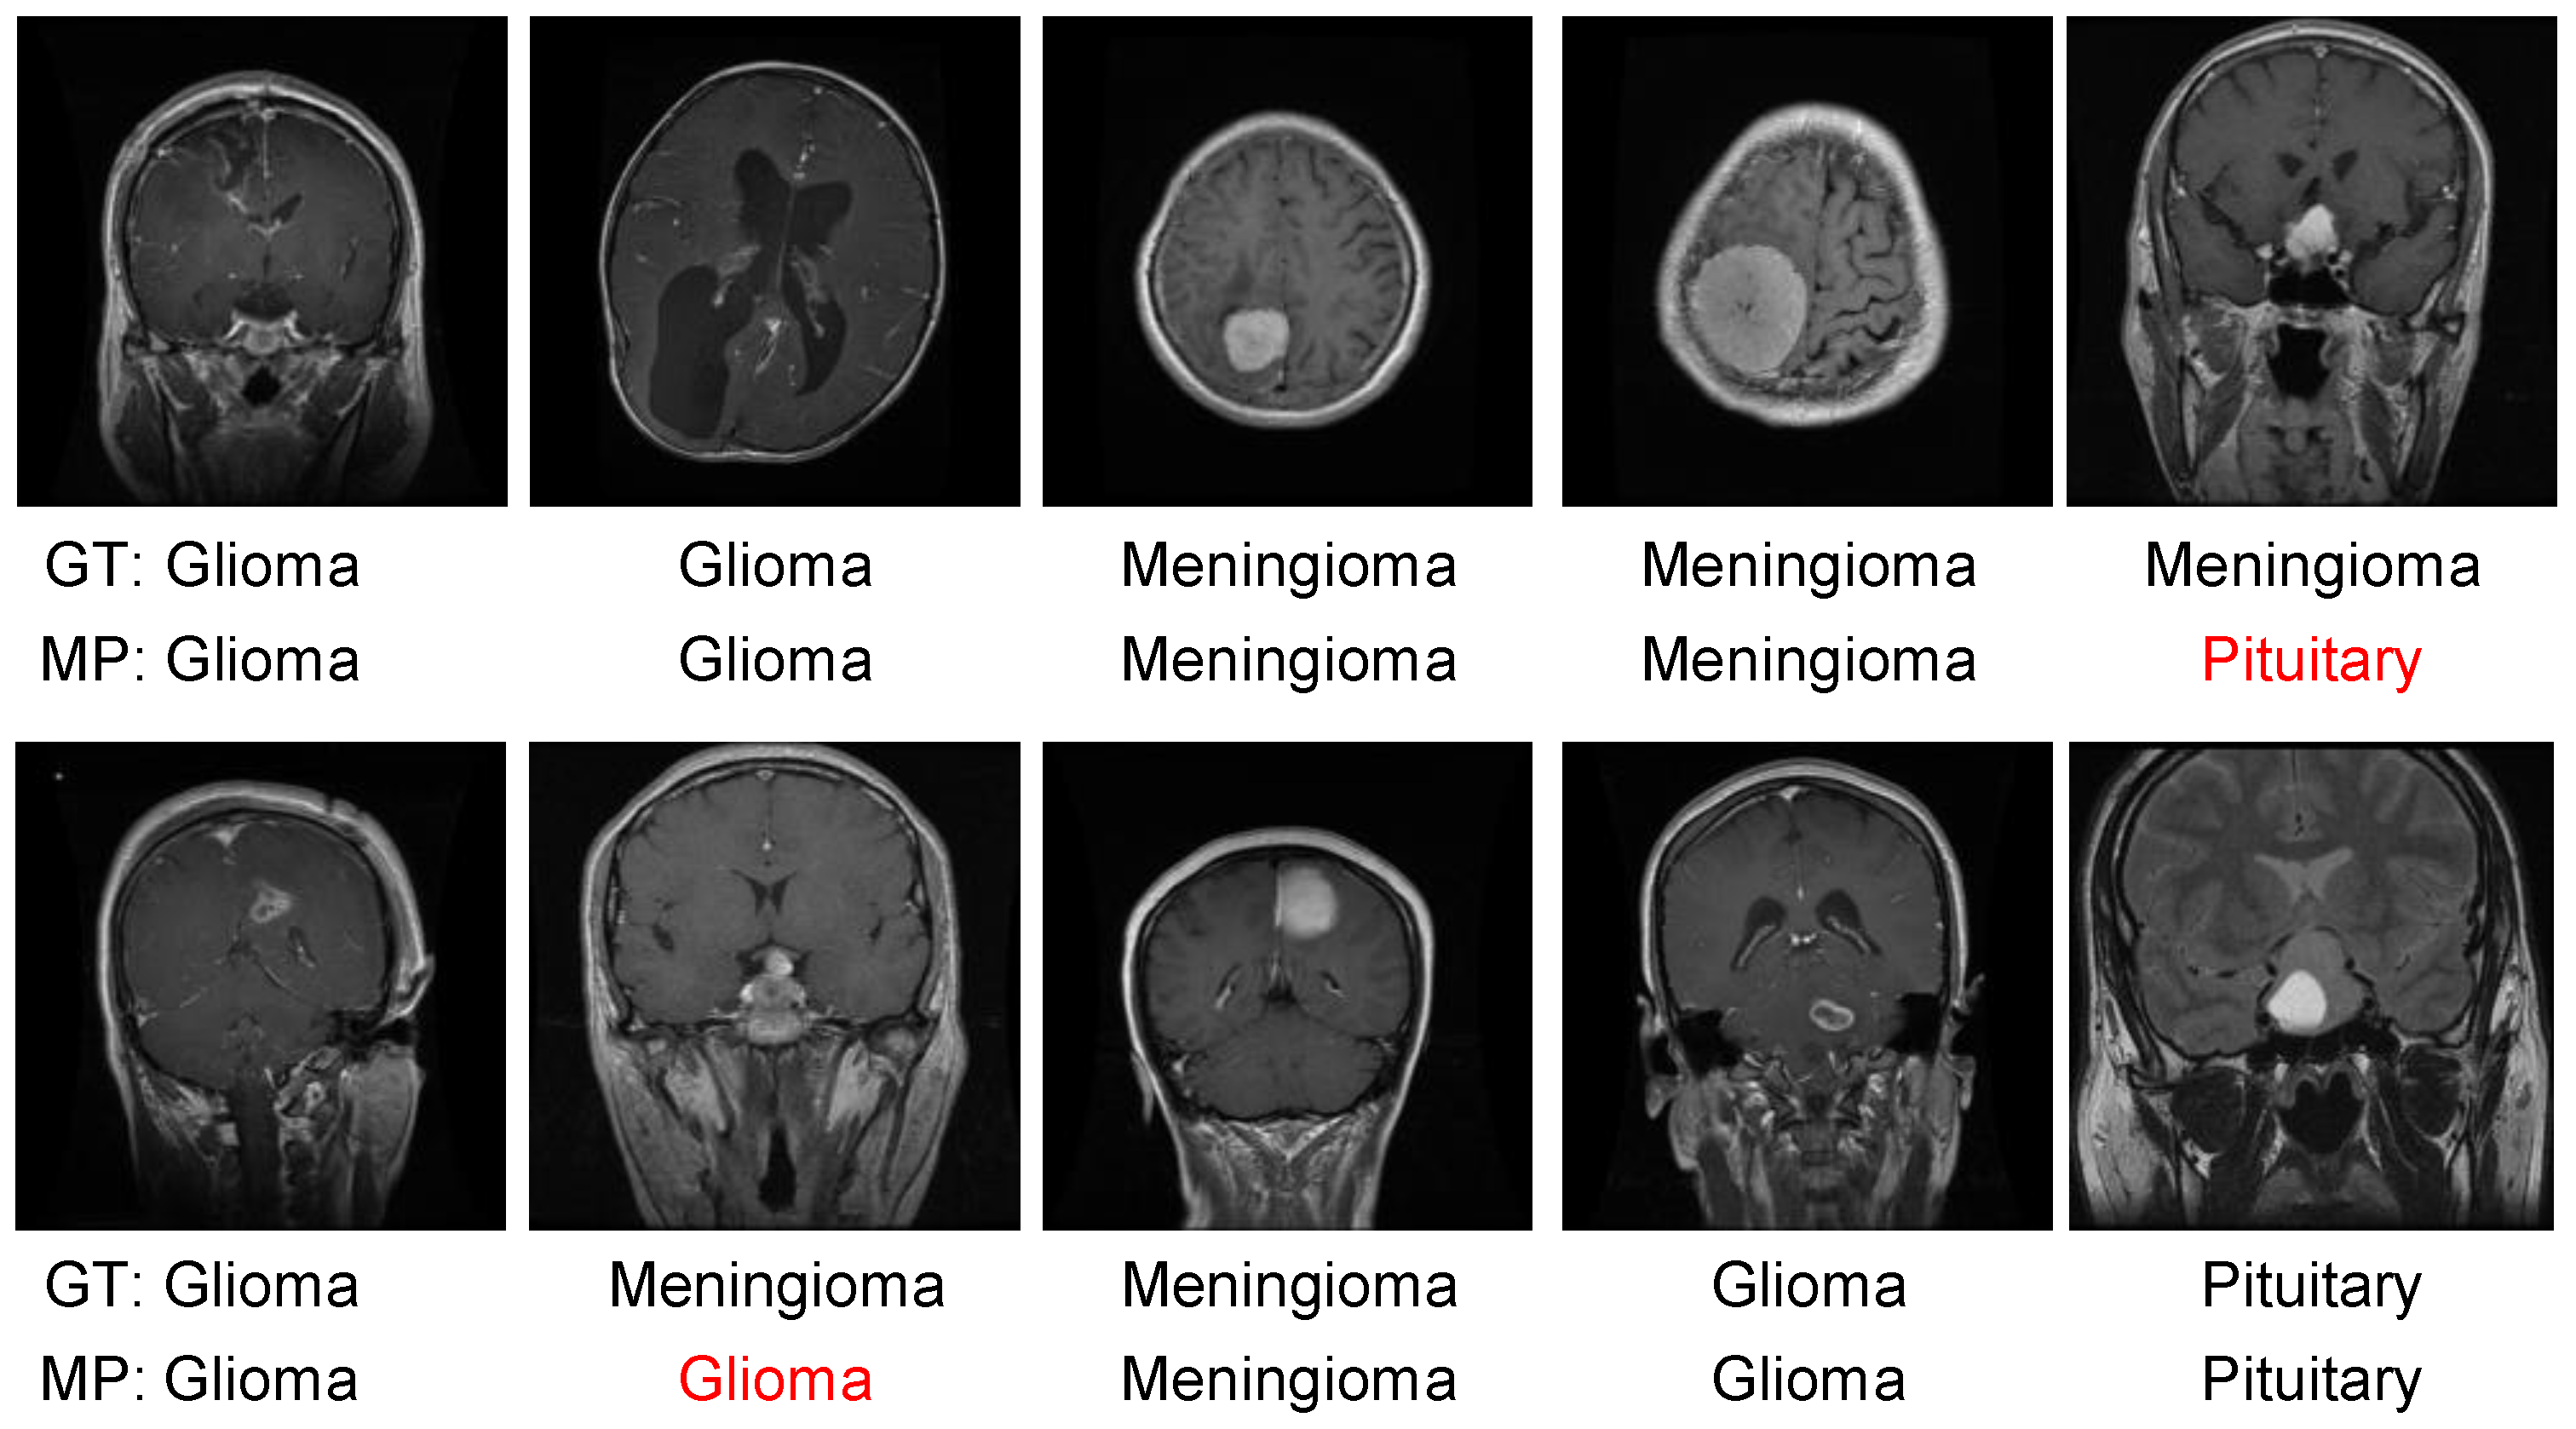

4.3. Results Evaluation Using BraTS 2018 Dataset

4.4. Results Evaluation Using Figshare Dataset